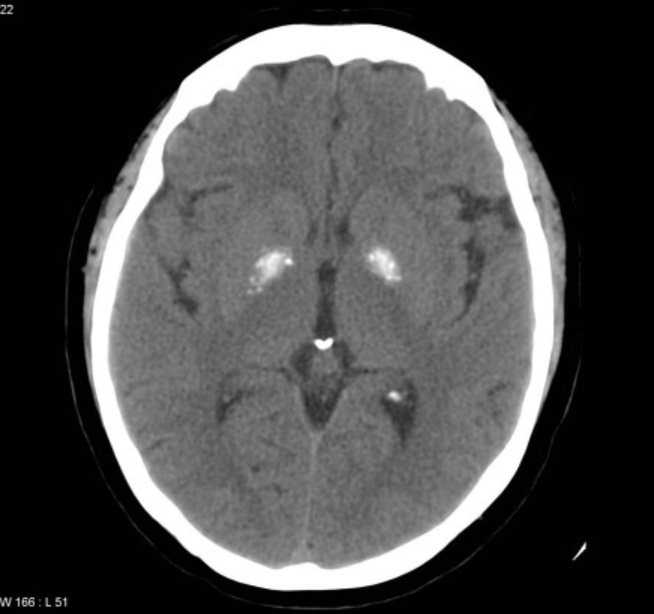

(1) 뇌 컴퓨터 단층 촬영

대뇌 석회화의 정도를 파악하고 평가하는 데 선호되는 방법입니다. 가장 빈번하게 영향을 받는 부위는 수정체 핵, 그 중에서도 내부 창백질이며 소뇌, 뇌간, 피질하 백색질도 영향을 받을 수 있습니다. 피각, 시상, 미상 및 치상 핵의 석회화도 일반적입니다. 칼슘 침착은 기저핵 외부의 영역에서 시작되거나 우세하며, 석회화는 점진적입니다.